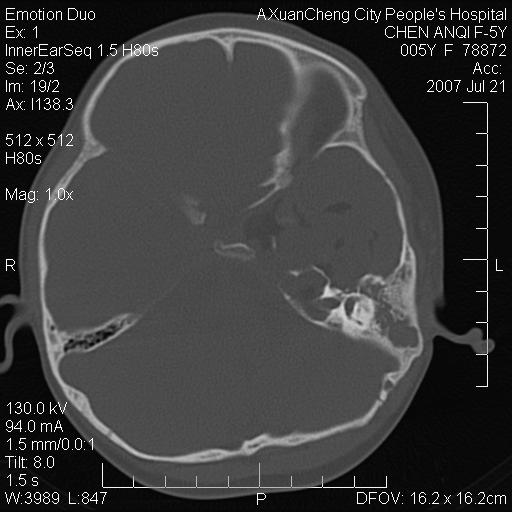

标题: PED0273:5岁,左耳流脓痛疼一周,颅底骨质破坏 [打印本页]

标题: PED0273:5岁,左耳流脓痛疼一周,颅底骨质破坏

患儿5岁,左耳流脓痛疼一周,左外耳道肉芽组织填塞 软组织窗显示病灶内结节状低密度影为气体密度

左侧中耳炎并胆脂瘤,左颞骨岩部骨质破坏并颅内感染积气。

考虑化脓性中耳乳突炎伴胆脂肪瘤形成并左颞叶感染,不除外合并嗜酸性肉芽肿.